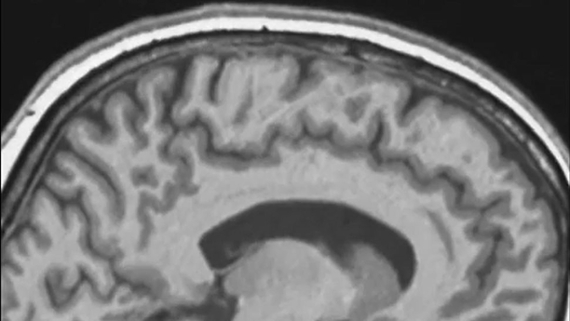

Spaceflight makes astronauts' brains move inside skulls

Space apparently changes your frame of mind in more ways than one.